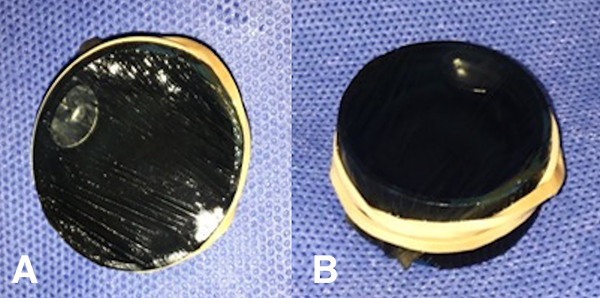

El modelo consiste en la utilización de un cerebro bovino (de preferencia utilizar la pieza completa) (fig. 1) y de pequeñas unidades de membrana amniótica, que se colocan envolviendo las tapas de botellas de plástico, para permitir la fenestración y dilatación de la misma (fig. 2 a-b). Éstas se disponen dentro de un recipiente esférico de poliestireno expandido (fig. 3 a-b), el cual se fenestra en la parte superior para permitir el ingreso del endoscopio. Para poder utilizar el monopolar debe colocarse dentro del recipiente el terminal del cable, que proviene de la consola, directamente en contacto con el tejido cerebral (fig. 4). Finalmente cerramos la esfera de poliestireno expandido y la llenamos por completo con solución fisiológica o agua corriente (fig. 5).

Para realizar la unidades de membrana amniótica utilizamos tapas de plástico color negro las cuales tapizamos del lado cóncavo con un fragmento de membrana amniótica de 5x5 cm. Para mantener la tensión utilizamos una banda elástica (fig. 2 b). Debemos rellenar la cavidad que quedó entre la tapa y la membrana amniótica con agua o solución fisiológica para lograr el medio acuoso que se encontrará una vez fenestrada la membrana y que simula el piso del III ventrículo (fig. 6). Para concluir colocamos la esfera sobre otro recipiente que sirve como base de sustentación y en la parte superior, donde teníamos las dos fenestras, colocamos dos trocares para el ingreso del endoscopio (no son requisito absoluto). Se utilizan dos entradas para duplicar el número de ejercicios (fig. 7). Este modelo innovador permite la biopsia y coagulación de tejidos (fig. 8) y la dilatación de membranas simulando un ejercicio de tercer ventriculostomía endoscópica.

Figura 2: Membrana amniótica. A) La imagen muestra el resultado final de la membrana amniótica envolviendo la tapa de gaseosa, se puede observar por translucencia que se encuentra llena de líquido. B) En la visión lateral se puede observar la tapa de gaseosa sujetada con una banda elástica